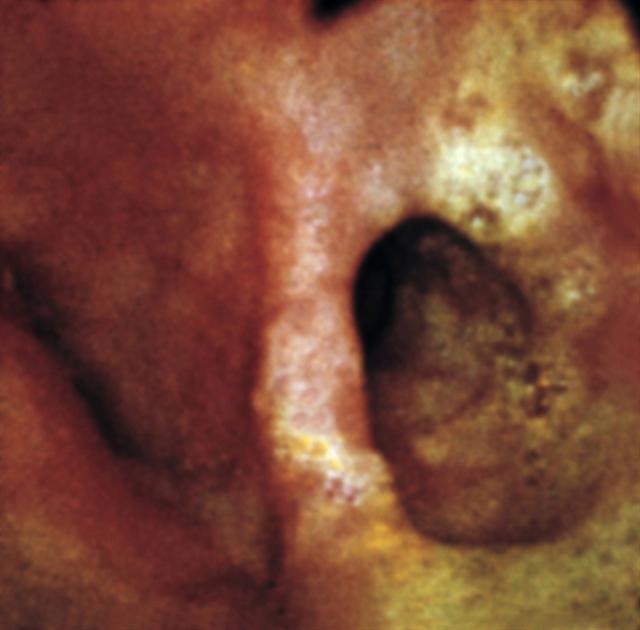

Рис. 9. Эндоскопическая картина тракционного дивертикула пищевода.